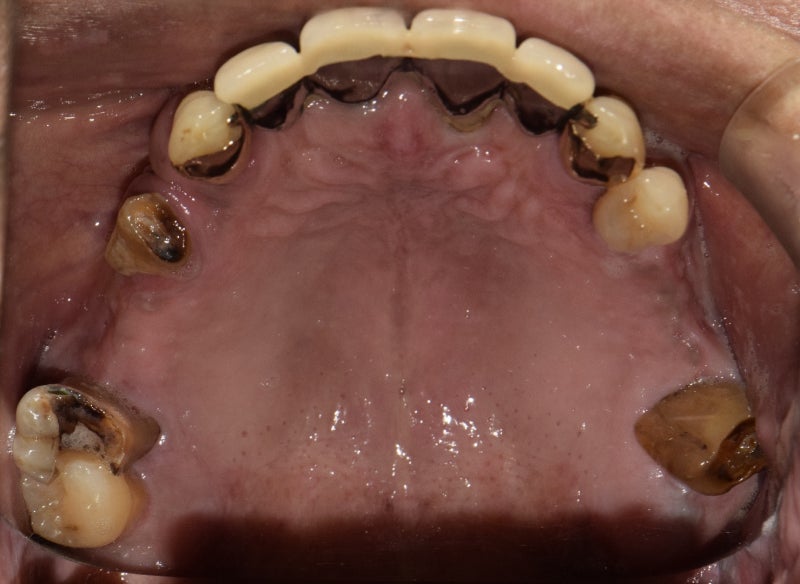

부산 임플란트 치과 치료를 잘하는 곳의 리뷰를 소개합니다.60대 남성 윗니 전체 11개 식립치료 기간 : 6개월 이상 포스트 투함 전 부작용 공지! 임플란트 치료 시 부종, 출혈, 감각이상 통증 등 후유증이 발생할 수 있습니다!21년 5월에 동래구에 살았던 분이군요. 왜 그런지 모르겠지만 윗니 이빨이 거의 남아 있지 않았군요. 이런 상태면 씹는데 너무 불편함을… 씹을 수 있어야겠네요 그리고 평소에 흡연을 많이 하시는 것처럼 보였어요. 흡연은 치아나 건강에 좋은 것은 하나도 없는 것 같습니다] 되도록 금연하세요!] 보시는 것처럼 만성 치주염에 완전하지 않은 치아는 발치가 필요해 보입니다. 남아있는 앞니조차도 위험한 상황이네요.

윗니를 윗턱이라고 합니다. 상악 기준으로 오른쪽, 왼쪽 모두 상악동 거상술이 필요해 보입니다. 그리고 상태가 안 좋은 앞니는 제거하기로 했어요. 거의 완전하지 않았기 때문에 발치가 필요했어요. 치료계획입니다. 상악잔존치발치치료 만성치주염치료 좌바로상악동서상술+골이식+임플란트식립우상악동서상술+골이식우3개월후임플란트식립보철치료후마무리오른쪽은골이식량이많이필요해보여서완전히회복될때까지기다려보기로하였습니다.